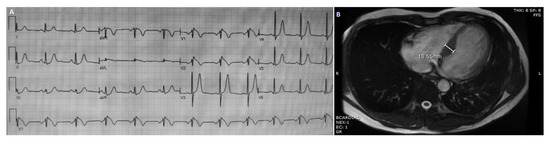

3.1.2. Patient 2

| P2 | M | 56 | Spontaneous | + * | Asymptomatic except for sporadic extrasistoles. Instrumental signs of HCM. | MYBPC3 | int 16 c.1458-1G > A | p.? | P | P | PVS1-PP5-PM2-PP3 (P) | [18] |